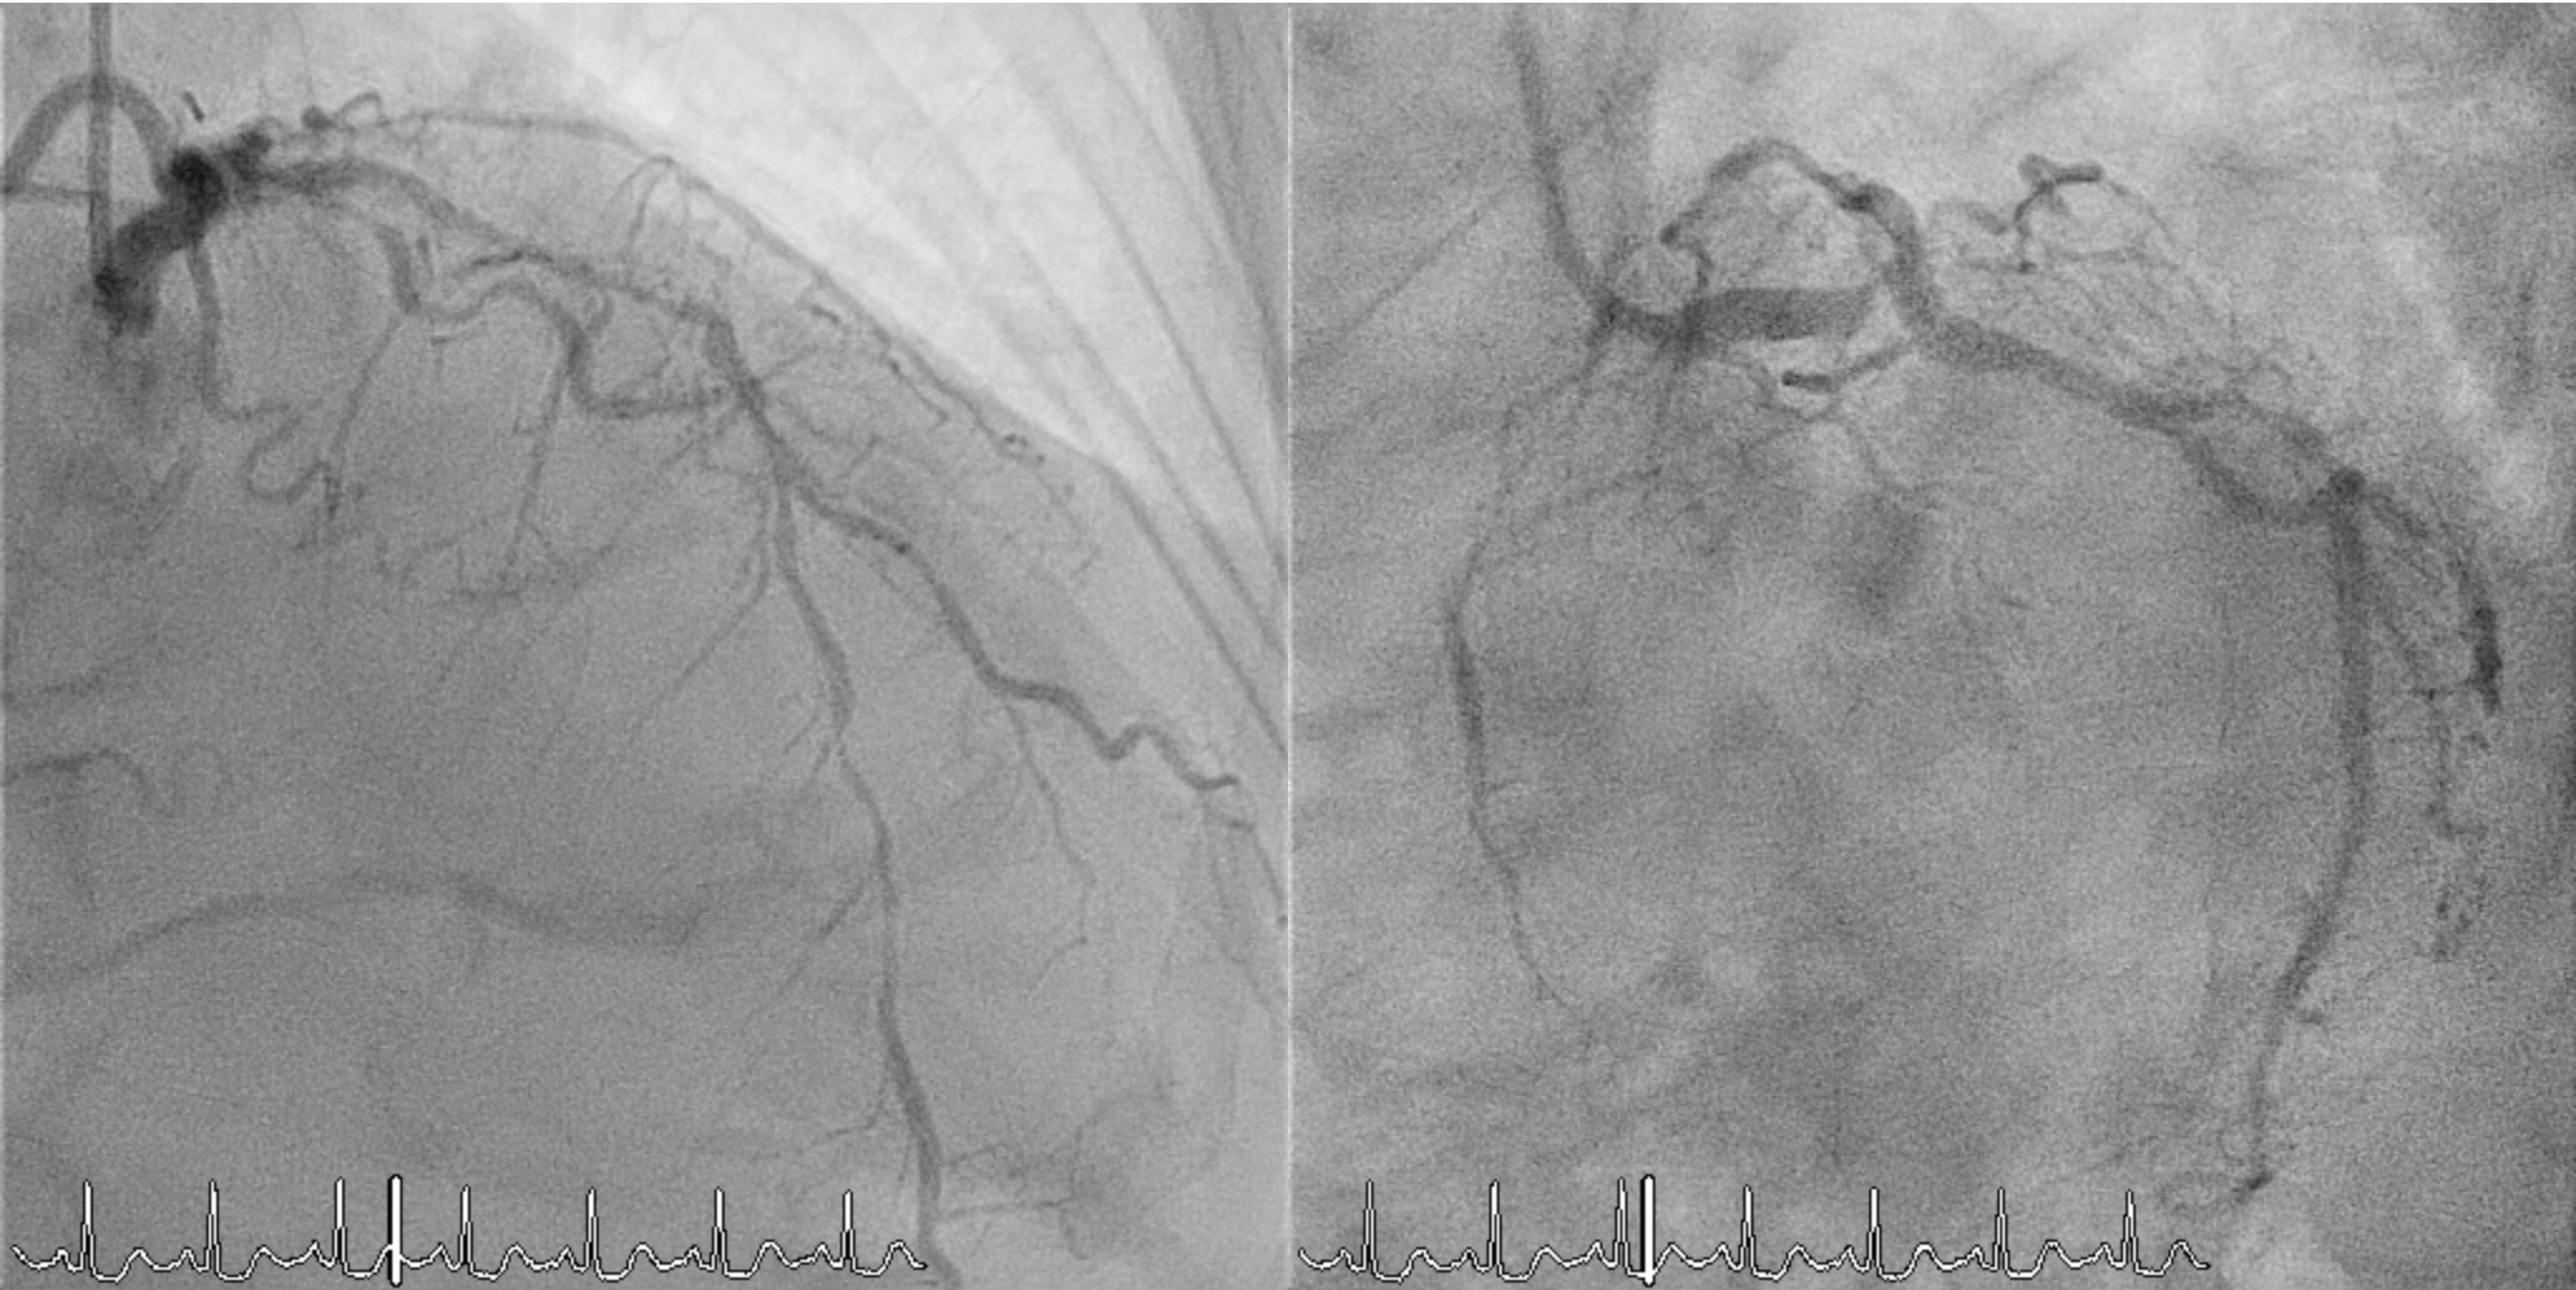

Coronary angiography revealed complex multivessel disease, with a syntax score of 42 points. The LMCA had a distal 95% eccentric lesion (Medina 1,0,0). The LAD showed diffuse disease with 70% stenosis proximally and 80% distally. The LCx had a proximal 90% and mid–distal diffuse 90% stenosis, with the OM showing a 70% proximal–mid lesion. The RCA had a proximal 85% and mid–distal 60% stenosis, and the small PDA had an 80% proximal lesion.

0502_02A.mp4

0502_02B.mp4